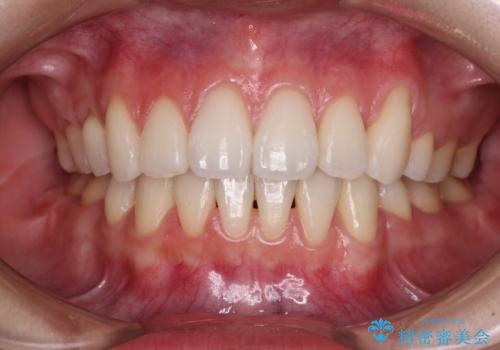

- 八重歯や前歯のデコボコを気にして来院された患者様です。

目立たない装置を希望されたので、上顎が裏側装置のハーフリンガルを選択し、上下左右の小臼歯(計4歯)を抜歯して矯正治療を行うこととしました。

デコボコが強い一方で出っ歯ではなかったため、抜歯したスペースを容易に閉じることができ、短期間での治療となりました。